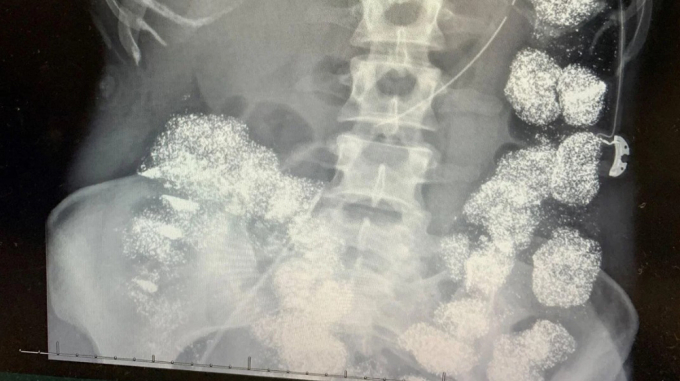

Kết quả xét nghiệm cho thấy nồng độ chì trong máu Pettey vượt mức 80 mcg/dL, gấp 8 lần ngưỡng an toàn. Phim chụp X-quang ghi nhận kim loại nặng lấp đầy đại tràng và dạ dày, thậm chí xâm nhập vào xương. Các bác sĩ nhận định bệnh nhân không thể vô tình nuốt lượng chì lớn như vậy nên lập tức báo cảnh sát điều tra người thân.

Hình ảnh X-quang cho thấy cơ thể Hannah Pettey bị lấp đầy bởi chì. Ảnh: Hartselle Police Department